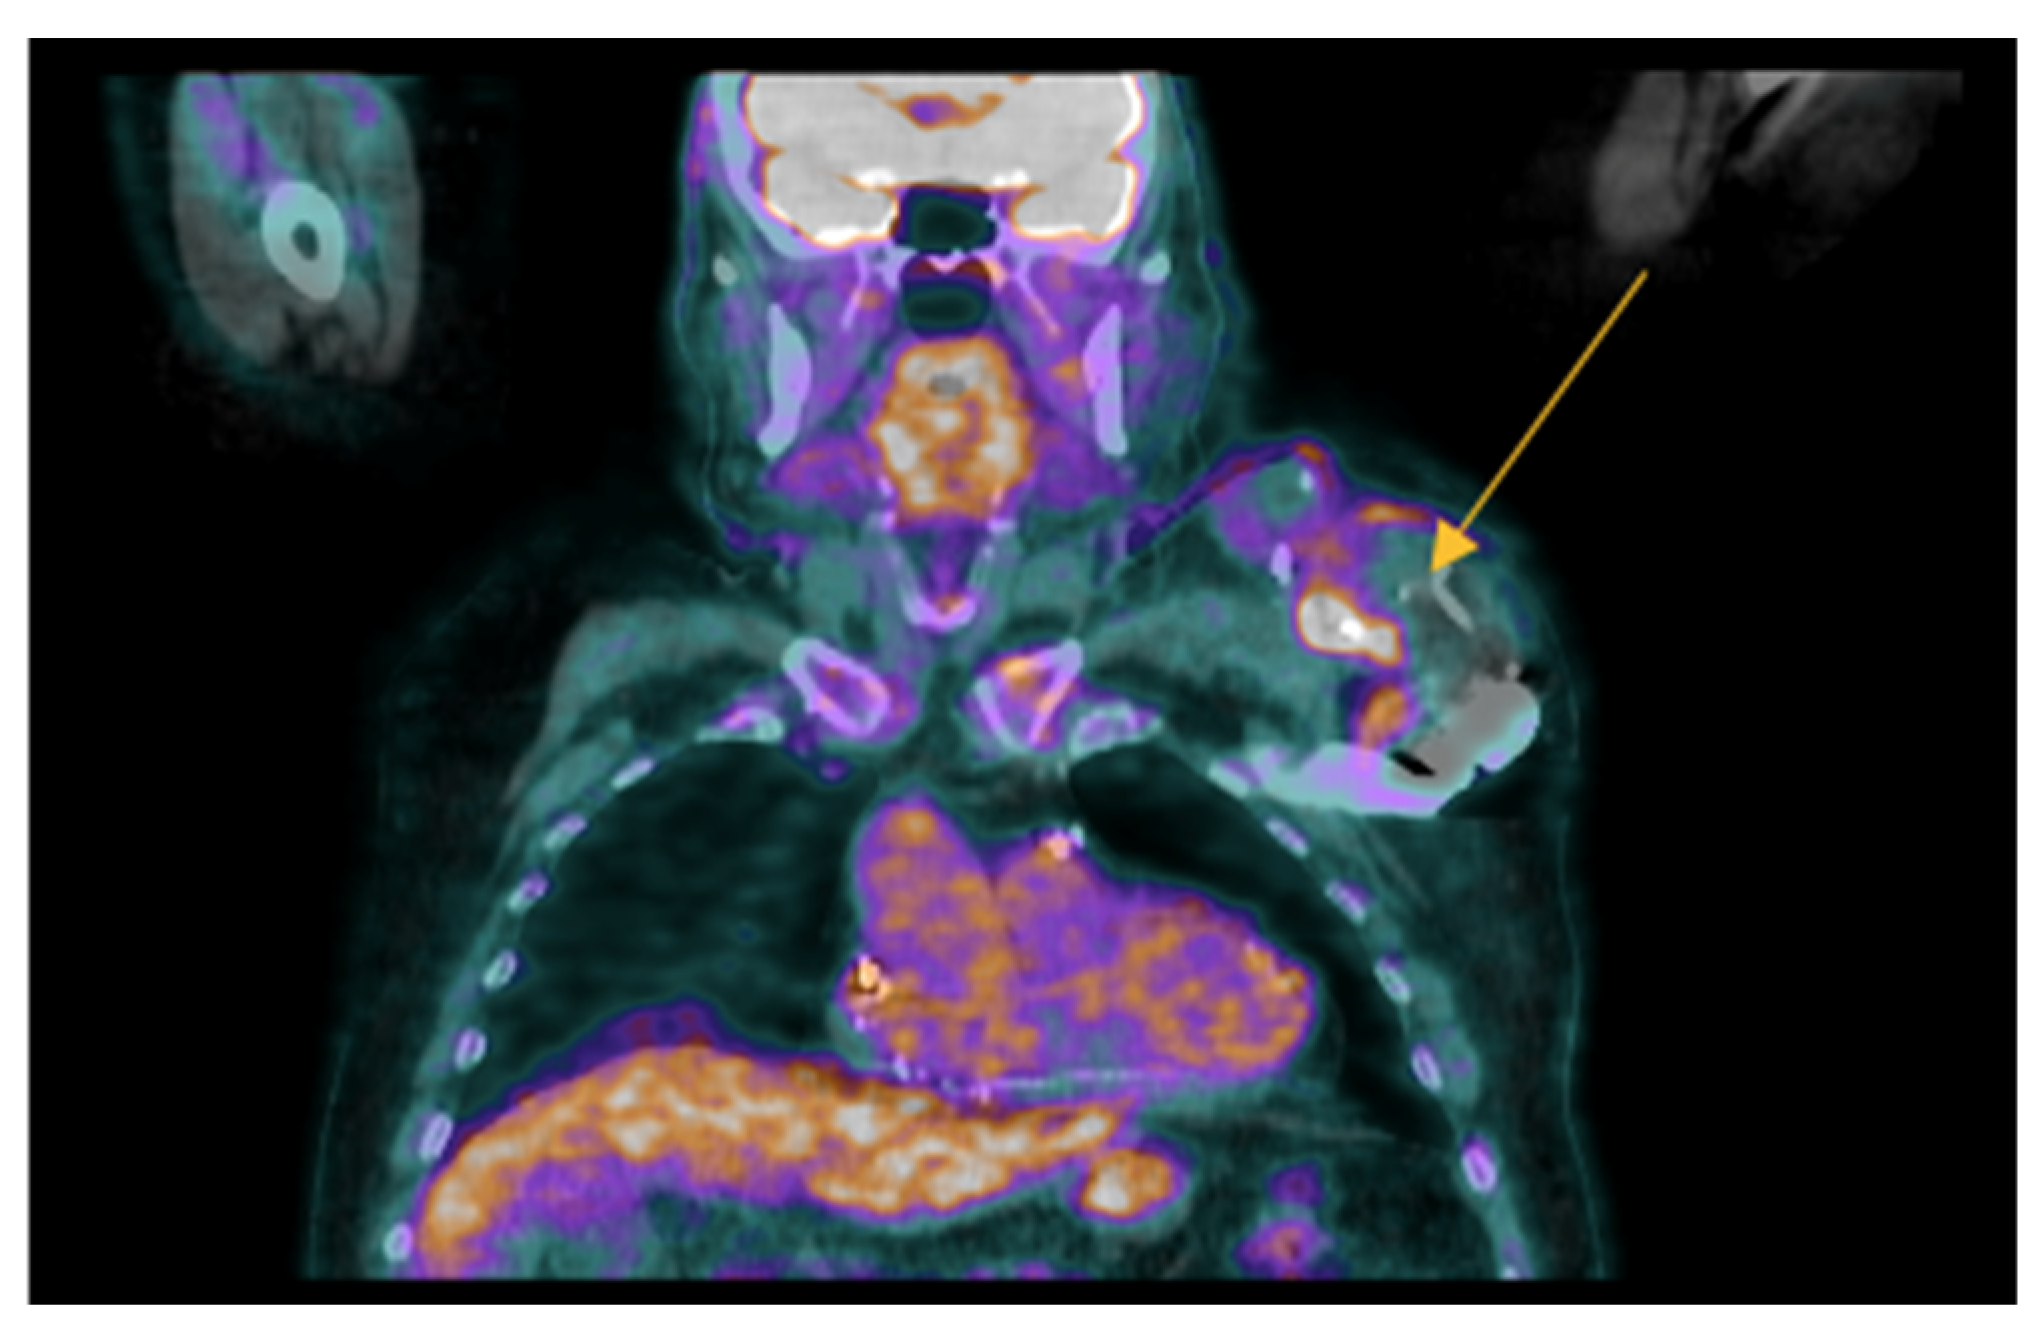

- Uncovering hidden infectious spread: FDG-PET/CT can also detect clinically silent disseminated infectious disease, identifying primary infection source, and/or septic embolism, which can be crucial for diagnosis and guiding patient management.

- Mikail, N.; Benali, K.; Mahida, B.; Vigne, J.; Hyafil, F.; Rouzet, F.; Le Guludec, D. 18F-FDG-PET/CT Imaging to Diagnose Septic Emboli and Mycotic Aneurysms in Patients with Endocarditis and Cardiac Device Infections. Curr. Cardiol. Rep. 2018, 20, 14. [Google Scholar] [CrossRef] [PubMed]